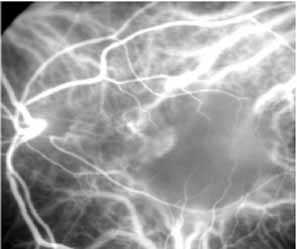

ICG angiography in amelanotic melanomas reveals variable blockage, depending on the amount of pigmentation present in the lesion. Corkscrew vessels have been identified with ICG angiography, but not with fluorescein angiography, in some patients with amelanotic melanoma80,81 (Fig. 24). The meaning of this vascular pattern currently is unclear, but it may eventually assist in the differentiation of these primary ocular tumors from metastatic lesions.

Fig. 24 A. Clinical photograph of a patient with an amelanotic melanoma adjacent to the optic nerve head. B. Mid-phase indocyanine green angiogram demonstrating corkscrew vessels within the melanoma.